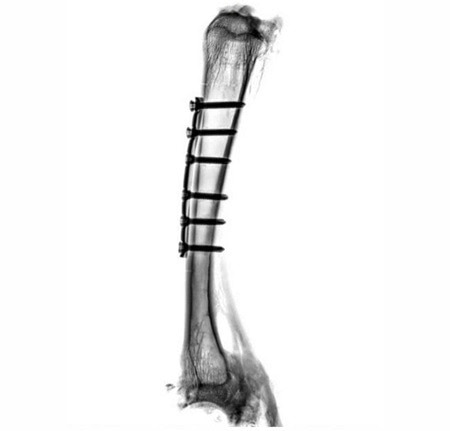

Implants on a sheep bone. The fit of the implants, the progress of healing and fissures on the screw connections are clearly visible.

Implants on a sheep bone. The fit of the implants, the progress of healing and fissures on the screw connections are clearly visible. Image Credit: Scintica Instrumentation Inc